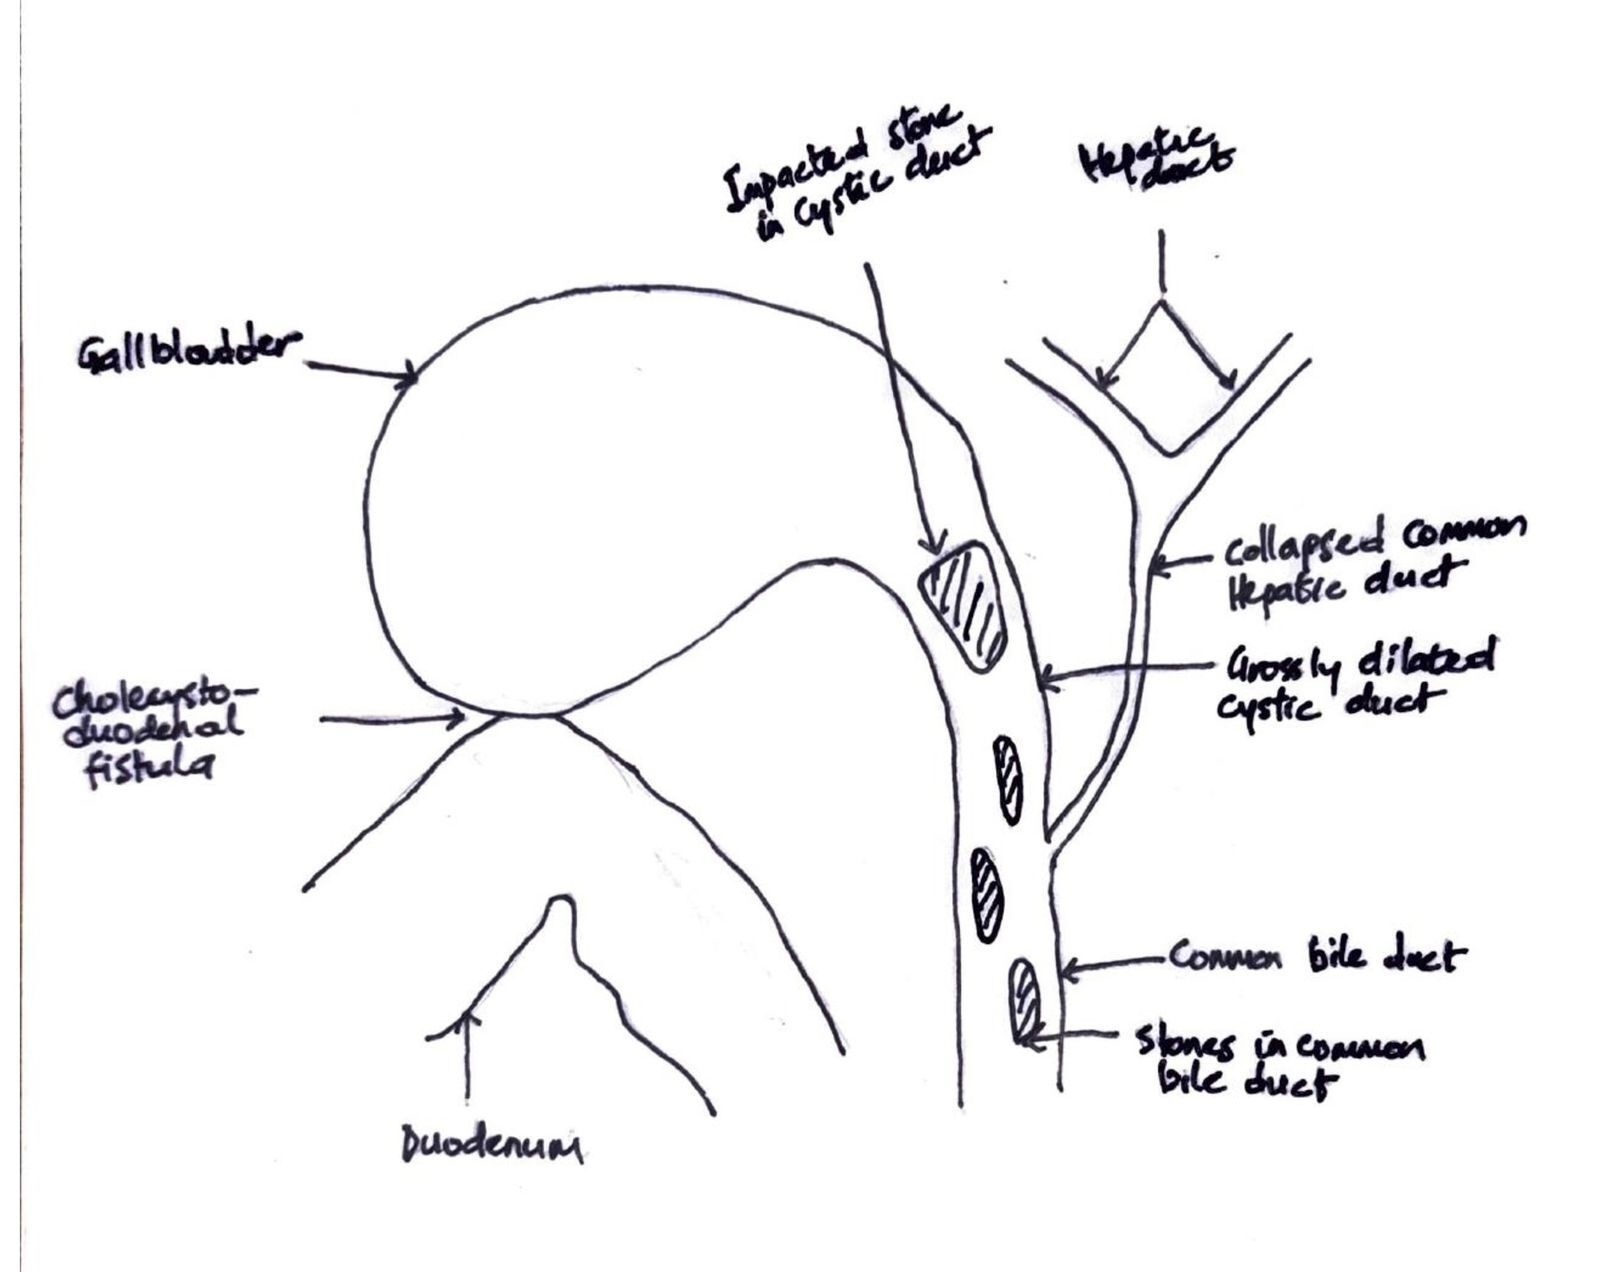

On examination, she was in fair general condition, afebrile and not icteric. The abdominal exam was normal. All relevant laboratory investigations were within normal ranges, and we proceeded with laparoscopic cholecystectomy. Intraoperatively, we noted extensive adhesions involving the gallbladder, omentum, and bowel. The gallbladder was firmly adherent to the cystic plate, rendering the surgery difficult. This prompted the team to opt for a bailout subtotal cholecystectomy. After dividing the gall bladder at the neck, a cholecystoduodenal fistula (Figure 3) less than 5mm was noted along with some bile leaks in the surgical field, reducing visibility. This led to the conversion to an open procedure through a midline incision. The duodenum was primarily repaired and secured with a pedicled omental flap. In an attempt to clearly define the biliary tree anatomy, we decided to explore the CBD. We made a 2cm incision on the anterior aspect of the CBD, which revealed a patent plastic stent in situ and multiple stones. The cystic duct was grossly dilated and found to be in continuity with the CBD. It contained multiple impacted stones, the largest measuring approximately 3cm. All stones were successfully extracted. A bile leak was noted at the cystic stump and was repaired primarily. The CHD was almost collapsed. The presence of a cholecystoenteric (cholecystoduodenal) fistula in a context of MS without gallstone ileus made us classify this as a Type 5A according to Csendes classification (Figure 4). The CBD was then repaired primarily. Abdominal irrigation was done, and a drain was left in situ. Postoperative monitoring was negative for bile leaks. The patient improved clinically, with liver function test normalising and was discharged after 10 days. Clinic follow-ups were scheduled every 3 months. The patient remained asymptomatic and is currently doing well and improving.